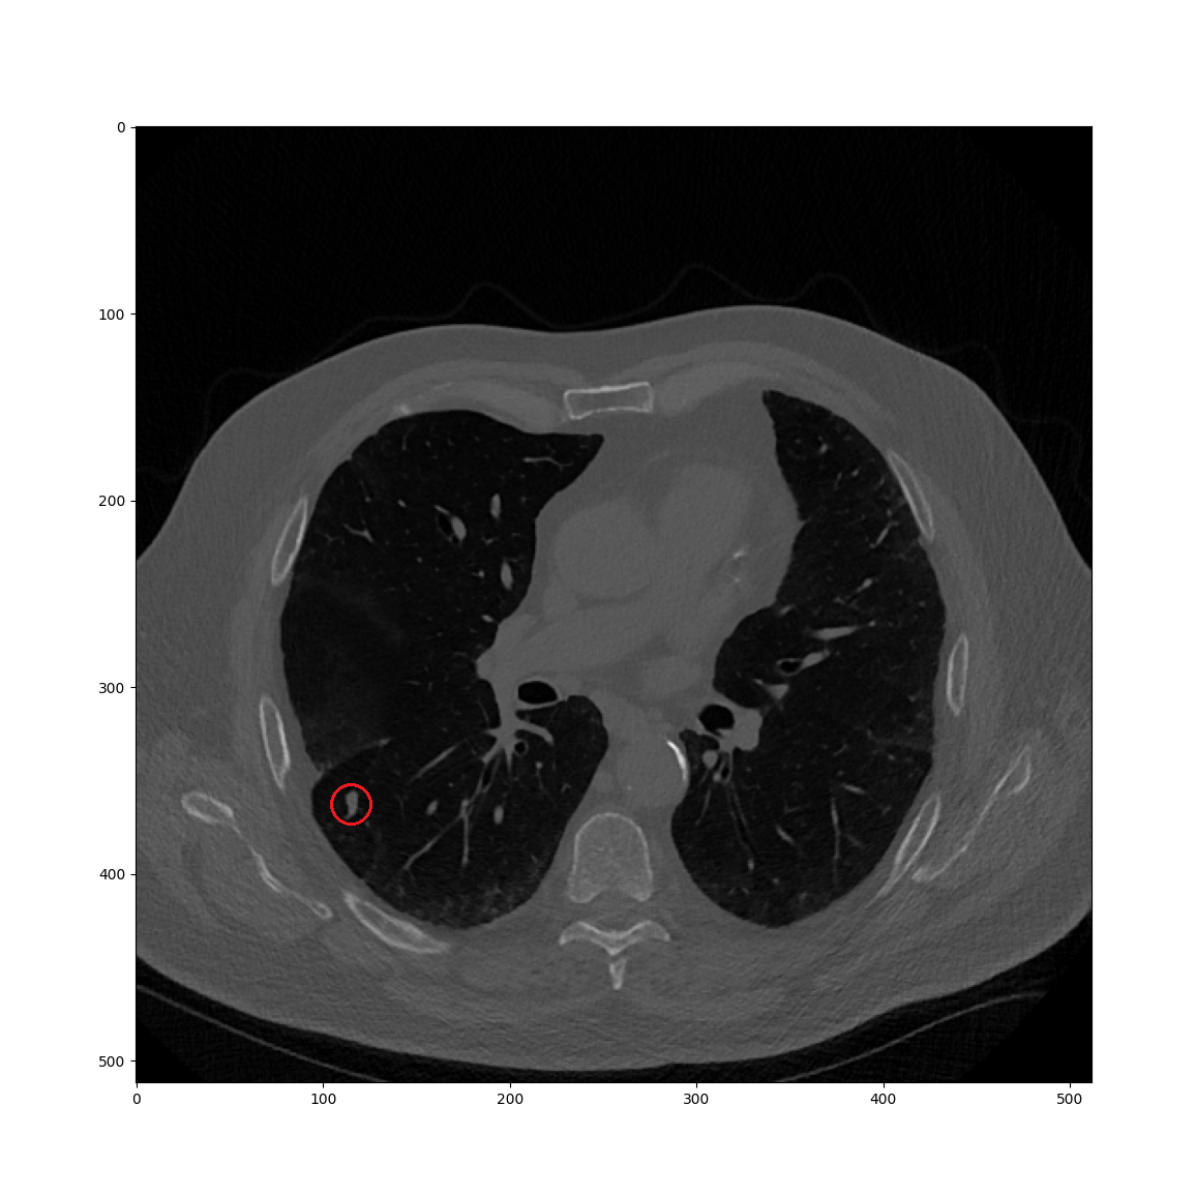

In Figure 2(a), there is a lung nodule at the point of interest of the current CT volume as an example of query point. The task is finding the corresponding location in the prior CT volume as shown in 2(b). In the first level, similarities are computed in every location of the 16mm grid which could be seen as a low-resolution heatmap as in 2(c). Then, until the fifth level, the maximum similarity location is used to continue the search in the next level while reducing the size of the search region. The resulting heatmap is given in Figure 2(d). The similarity in the finest level precisely describes the nodule location. There are two different characteristics as compared to the deep learning-based descriptor search approach [17]. First, the finest similarity is not computed on the whole image but on a specific location conditionally on the previous maximum. Thus, our algorithm is computationally faster, even on the CPU. Also, the descriptor is based on a predefined sampling model, which does not require optimization in training time or any additional computation for feature extraction in the runtime.